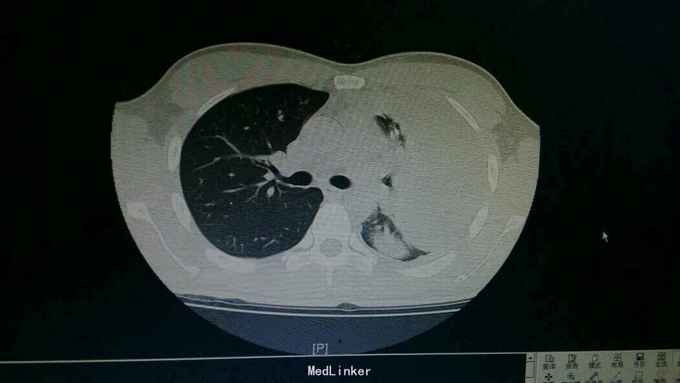

查体:神情,左侧呼吸运动减弱,叩诊浊音,左肺呼吸音低,右侧呼吸性正常。 辅查:胸部CT:左侧大量胸腔积液,左肺受压实变。复查胸片:左侧胸腔积液减前好转。胸水提示渗出性胸腔积液,淋巴细胞为主。T-SPOT:A:64个,B:42个。

诊断:结核性胸膜炎。 治疗:入院结合予以抗结核治疗,胸腔穿刺引流术。